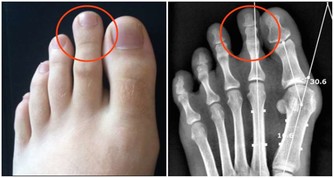

飲用方法: 1.每日約一杯(50毫升),年紀大的人每次20毫升左右; 2.每日飲一至兩次; 3.浸過酒的洋蔥片一起食用更好; 4.不喝酒的人,可用兩倍左右的開水稀釋後飲用或每次倒入電鍋內煮約4至5分鐘,蒸發酒精後飲用。 5.若然喜歡甜的,可加入一點蜂蜜。 紅酒泡洋蔥在日本非常流行!它究竟能治哪些病? 一. 高血壓的患者,飲了之後血壓正常且安定,還能降低糖尿值,降低血糖。 二. 最妙的是對老花眼也有很大的改善,長期飲用後不用戴眼鏡也可以閱讀一般的周刊、雜誌。 三. 每晚都要去幾次廁所的夜晚頻尿症,喝了兩天後,不可思議地恢復正常了。 四. 每天夜裡醒來,一直到天亮都不能再入睡的,或者不吃安眠藥就睡不著的失眠族,飲用後也會逐步緩解失眠症狀。 五. 眼睛疲勞後看東西模糊不清,喝了之後第二天就好多了。 六. 經常肚子會脹,有便秘的人,喝了後第二天便可正常排便。 花錢不多又簡單的方法,功效很顯著,不妨一試哦! 討厭吃洋蔥嗎?看看下面的文章,即使它不那麼可口,為了身體好,也請多多食用! 【洋蔥比骨質酥鬆症的藥有效】 很多人不愛用洋蔥做菜,切的時候會讓人流眼淚,很多人也很討厭洋蔥味。但是想要讓自己骨骼結實、身體長得高、預防骨質酥鬆症的人,最好還是乖乖地捏著鼻子吃洋蔥吧。因為權威期刊「自然」的最新研究報告指出,洋蔥是最能夠防止骨質流失的一種蔬菜。洋蔥預防骨質流失的效果,甚至比骨質酥鬆症治療藥品還要好! 【洋蔥可以預防膽固醇過高】 據哈佛醫學院心臟科教授介紹,每天生吃半個洋蔥,或喝等量的洋蔥汁,平均可增加心臟病人約30%的HDL含量(HDL為高密度脂蛋白膽固醇,一種被認為有助於預防動脈粥狀硬化的膽固醇,也是一種的好的膽固醇)有利於保護心臟。 【洋蔥可以分解脂肪】 克多博士讓診所里的心臟病人每天吃洋蔥,結果發現洋蔥里所含的化合物也能阻止血小板凝結,並加速血液凝塊溶解。所以,當你享用高脂肪食物時,最好能搭配些許洋蔥,將有助於抵銷高脂肪食物引起的血液凝塊。所以說牛排通常搭配洋蔥一起吃,是很有道理的。 【洋蔥可以預防胃癌】 洋蔥和大蒜、大蔥、韭菜這些蔥屬蔬菜,都含有抗癌的化學物質,研究人員在中國山東省一個胃癌罹患率很高的地方所做的調查發現,當洋蔥吃得越多,得胃癌的機率就越低。 【洋蔥可以對抗哮喘】 洋蔥含有至少三種抗發炎的天然化學物質,可以治療哮喘。由於洋蔥可以抑制組織胺的活動,而組織胺正是一種會引起哮喘過敏症狀的化學物質。另外根據德國的研究,洋蔥可以使哮喘的發作機率降低。